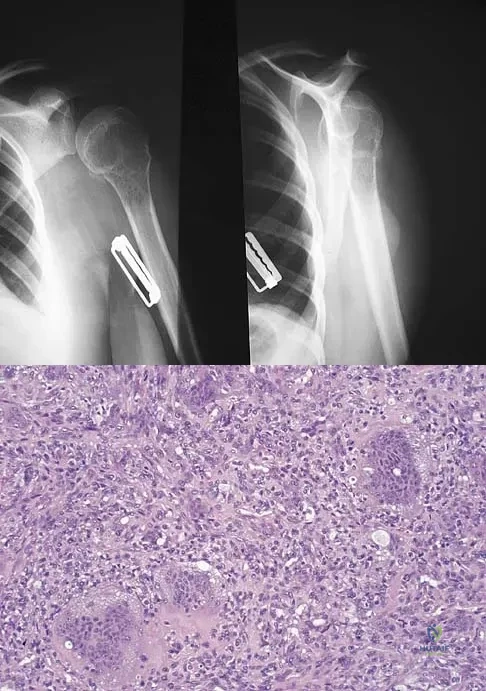

A 34-year-old woman reports constant midlateral arm pain after sustaining minimal trauma to the shoulder. Radiographs and a biopsy specimen are shown in Figures 29a and 29b. What is the most likely diagnosis?

A radiograph, MRI scans, and a biopsy specimen of a 9-year-old boy with thigh pain are shown in Figures 37a through 37d. Management should consist of